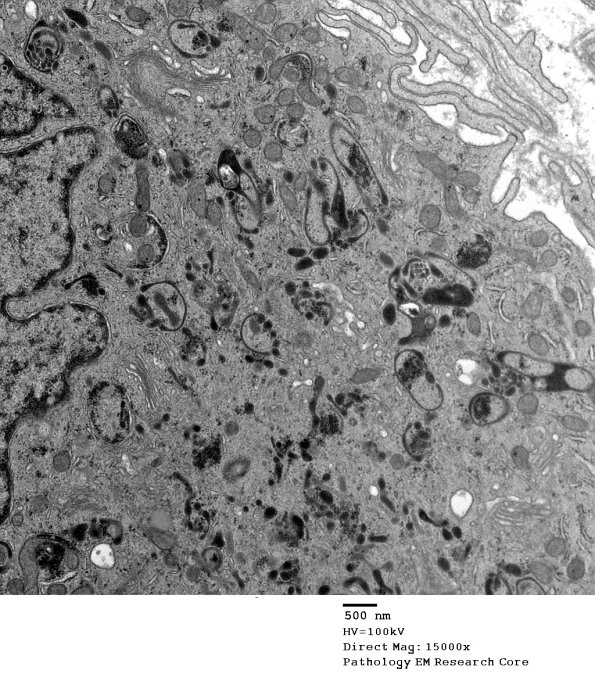

We have had some difficulties in identifying this cell and determining its importance, if any, to the understanding of this case. It is likely that this cell is a member of histiocytic/macrophage/dendritic cell group.